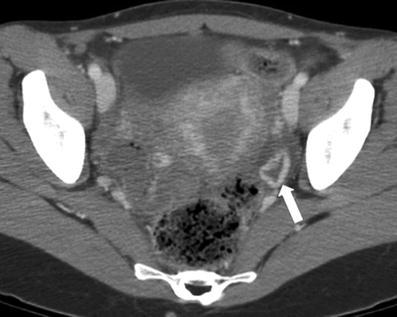

24 year old female with pelvic pain

Turbo-ovarian abscess

complex fluid next to the ovary w/appropriate history